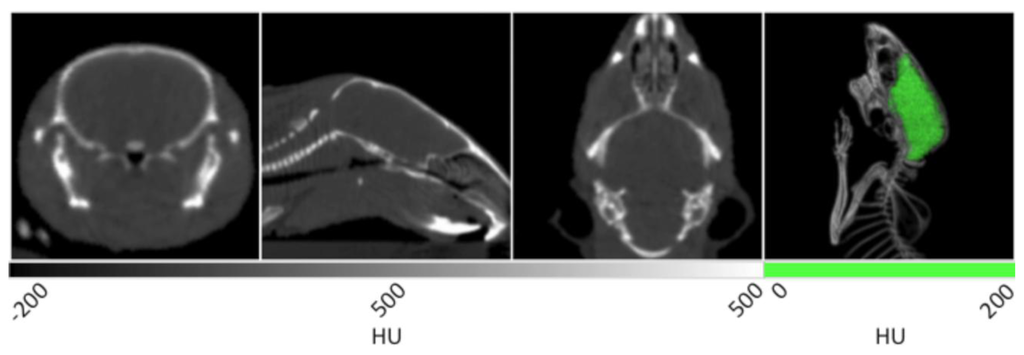

Without contrast enhancement, the brain can be distinguished from the cranium due to the stark differences in density between the tissue and surrounding bone. The first three panels of Figure 3 show the homogenous grey matter delineated by cranial bone. These frames also display many additional anatomical features. In the transverse slice at left, the trachea is seen as black due to negative contrast at the center of the frame. In the next image showing the coronal view, a larger portion of the trachea can be observed in addition to the nasal cavity and spinal cord. In the 3D rendering at right, the cranium is bisected to clearly show the brain tissue circumscribed by the skull. Because the cranium delineates the brain cavity, it enabled the manual segmentation of brain tissue. Manual segmentation refers to the creation of a VOI by manually drawing a region of interest (ROI) around each slice of the reconstructed brain data. After the VOI was constructed, the data was masked outside of it to isolate the brain tissue and display it in green within the context of the rendered animal CT. As noted above, the density values within the brain may be measured as a whole or in a region specific manner in different lobes.